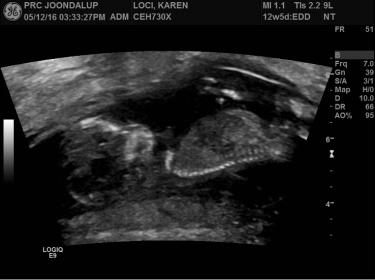

1st and 2nd pic is an internal ultrasound at 7 weeks